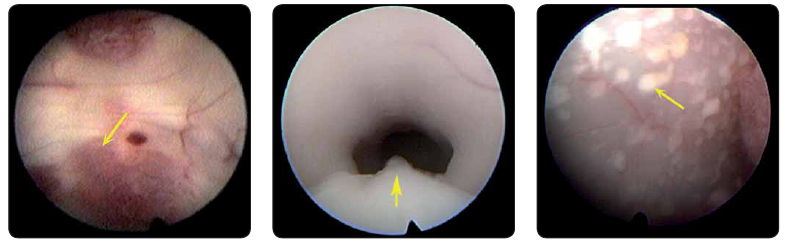

Při průkazu vícečetného nádorového postižení mozkových komor je nutné vzít v úvahu především metastatické postižení (obr. 1), ale diagnostická rozvaha by měla zahrnovat i multicentrický maligní gliom, mozkový lymfom, germinom, meduloblastom, subependymom, subependymální gigantobuněčný astrocytom, duplicity, ale také např. nodulární heterotopie. I při nepříznivé prognóze především nitrokomorových metastáz a nemožnosti radikální operace je nutné zvážit nutnost histologické verifikace lézí, která je rozhodující pro další onkologickou terapii, a řešení nitrolební hypertenze při blokádě mokové cirkulace. Oba úkoly může splnit neuroendoskopická technika, která navíc může upřesnit rozsah nádorového postižení komorového systému.

Do souboru bylo zařazeno 16 nemocných, 11 žen a 5 mužů, průměrný věk 51,2 let (16–82 let). Převládali nemocní s postižením obou postranních a III. komory (8 nemocných) a s postižením obou postranních komor bez postižení III. komory. Blokáda mokových cest nádorem byla při neuroendoskopické operaci řešena u 13 nemocných. U 8 nemocných byla neuroendoskopie dostačující, u 5 byl nutný shunt (subarachnoidální nádorový rozsev, rychlá progrese nádoru). Biopsie byla provedena u 14 nemocných a nebyla indikována u 2 pacientů (endoskopický obraz metastázy melanomu, četné drobné uzlíky u nemocné s diseminací karcinomu prsu) (obr. 2, 3). Diskrepantní výsledek byl u jediného nemocného (endoskopie astrocytom gr. II–III, stereotaxe glioblastom). Četnost komplikací endoskopií byla 0 %. U jednoho nemocného bylo nutné odstranit shunt pro infekt. Histologické vyšetření prokázalo metastatické postižení u 4 nemocných, B lymfom u 3 nemocných a glioblastoma multiforme u 3 nemocných.